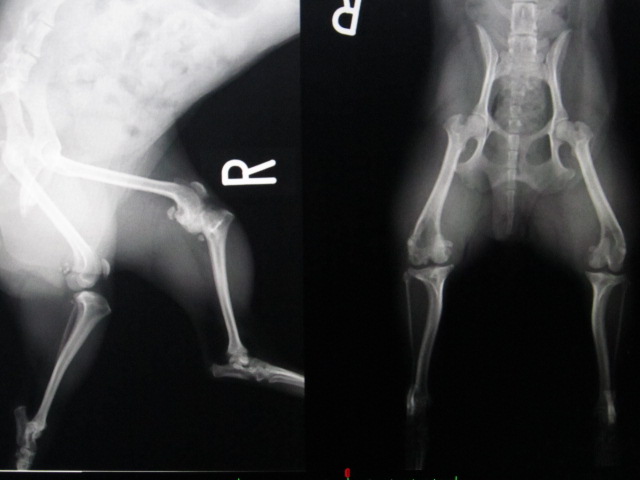

術後のレントゲンです。

右後肢は滑車造溝術と脛骨粗面転移術を行いました。

どちらの足も膝蓋骨がしっかりと大腿骨の滑車の上に乗っています。